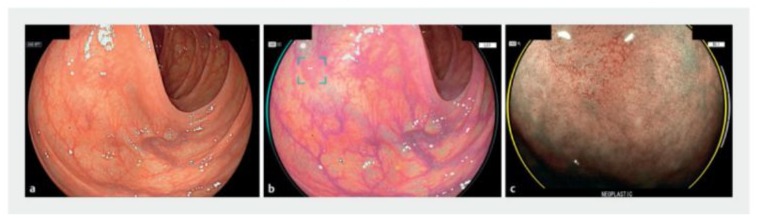

Beyond detection, AI can also assist in polyp characterization (CADx) during endoscopy. This involves determining, in real-time, whether a detected polyp is likely neoplastic (adenoma) or non-neoplastic (e.g., hyperplastic) based on its endoscopic features-effectively an optical biopsy. Studies have explored CNN models trained to classify polyp histology from high-definition endoscopic images. For instance, a multicenter trial of the Fujifilm CAD EYE system showed that the AI’s diagnostic accuracy for predicting polyp pathology was comparable to experienced endoscopists for diminutive polyps.

The AI system achieved ~80% sensitivity and 83% specificity in identifying adenomas, nearly matching expert endoscopists (88% sensitivity, 83% specificity) [5]. Notably, both AI and humans struggled with certain lesions like sessile serrated polyps, highlighting an area for improvement. The ability to accurately characterize polyps on the fly could support a “resect and discard” paradigm (where diminutive benign polyps need not be sent for pathology), potentially saving costs and time-but current AI accuracy, while promising, still requires improvement and validation in larger studies.

Several types of AI models have been used in colonoscopy: earlier approaches included traditional ML algorithms for frame classification, but modern systems predominantly use deep CNNs due to their superior image feature extraction [11]. Some detection models are based on architectures like YOLO (You Only Look Once) or SegNet for real-time object detection [1]. These run at video frame-rates to highlight polyps with boxes or markers during the procedure. Such systems have undergone regulatory approvals (the first FDA-cleared colonoscopy AI device was GI Genius in 2021) and are increasingly being adopted in practice. Key performance metrics from clinical trials include not only ADR, but also false-positive rate (AI can occasionally flag stool or folds as polyps). Fortunately, most studies report that while AI may increase the number of diminutive polyps detected (some of which might be clinically insignificant), the trade-off in false alarms is low and acceptable [1]. In summary, AI in colonoscopy has high sensitivity for polyp detection, improves consistency across endoscopists, and has demonstrated clear clinical utility by enhancing a crucial quality metric (ADR).